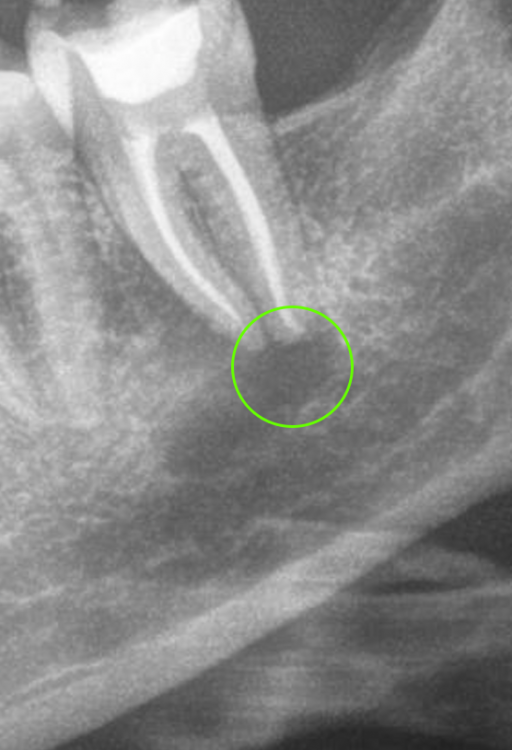

Начала ныть десна под депульпированной 10 лет назад нижней семеркой. Сделал панорамный снимок и под зубом штука похожая на кисту. Сходил на осмотр, на осмотре врач сказал что зуб слегка шатается, скорее всего у тебя под ним киста. Я показал снимок, врач сказал что да, это киста и посоветовал сделать КТ и сказал что нет проблем ее консервативно вылечить. (Распломбировать канал, положить лекарство и киста должна пойти на убыль). Но уже после НГ, сейчас все закрывается изза праздников.

Меня смущает форма кисты, она продолговатая, хотя по идее должна быть круглая. И темное пятно под кистой в челюсти (выделил красным). Или я непрвильно смотрю и киста это только то в зеленом кружочке?